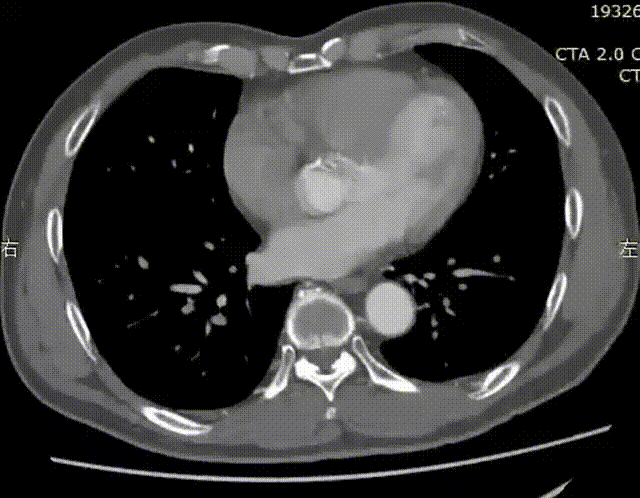

二、术前CT数据

患者入院后行CTA检查,CTA提示患者双侧巨大髂总动脉瘤,腹主动脉分叉以上血管直径正常。